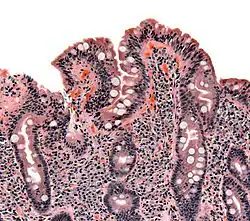

The ileocecal valve prevents reflux of bacteria from the colon into the small bowel. Resection of the valve can lead to bacterial overgrowth. | |

Finally, abnormal connections between the bacteria-rich colon and the small bowel can increase the bacterial load in the small bowel. Patients with Crohn's disease or other diseases of the ileum may require surgery that removes the ileocecal valve connecting the small and large bowel; this leads to an increased reflux of bacteria into the small bowel. After bariatric surgery for obesity, connections between the stomach and the ileum can be formed, which may increase bacterial load in the small bowel.[21]